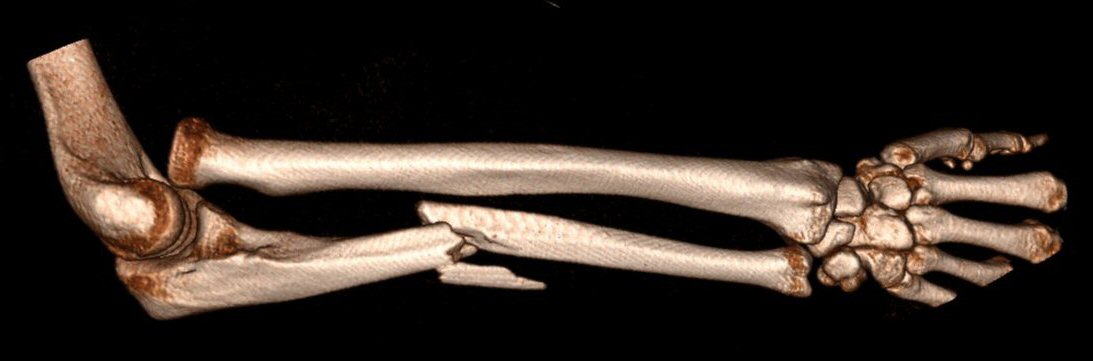

Monteggiafraktur: fraktur på ulna och samtidig luxation av caput radii. Man är inte helt överens om ulnafrakturen ska vara i den proximala tredjedelen eller proximala två tredjedelarna av ulna. Radiushuvudet kan också vara frakturerat istället för luxerat.

Monteggiafraktur